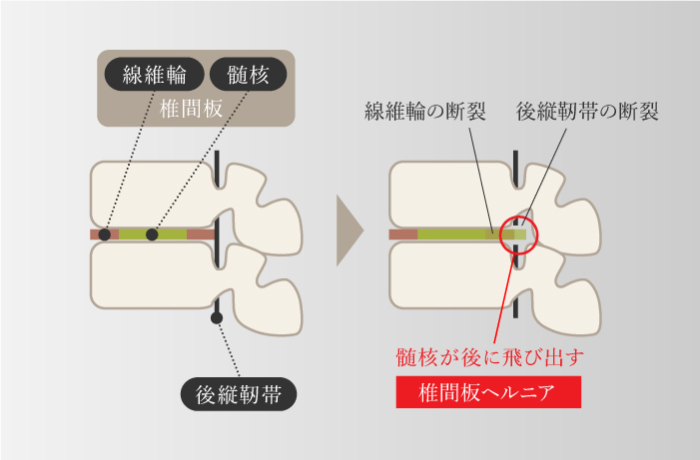

腰を曲げる動作が原因

-

腰椎が後方にシフトしてしまっているために症状がでます。